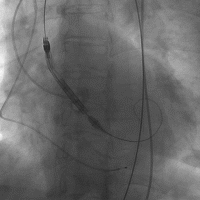

评估瓣环上结构后,选择合适尺寸的人工瓣膜(本病例植入VitaFlow™ 瓣膜),然后进行瓣膜置入及释放。瓣膜释放过程中需要团队精密的合作,第一术者和第二术者一前一后密切配合,控制手柄一步步释放,保证瓣膜良好的植入深度。瓣膜释放约四分之三,在人工瓣叶发挥功能后,进行造影,观察瓣膜位置是否恰当,然后完全释放。(Figure 11)

Figure 11

6. 球囊扩张评估瓣环上结构

7. 置入人工瓣膜

8. 置入人工瓣膜